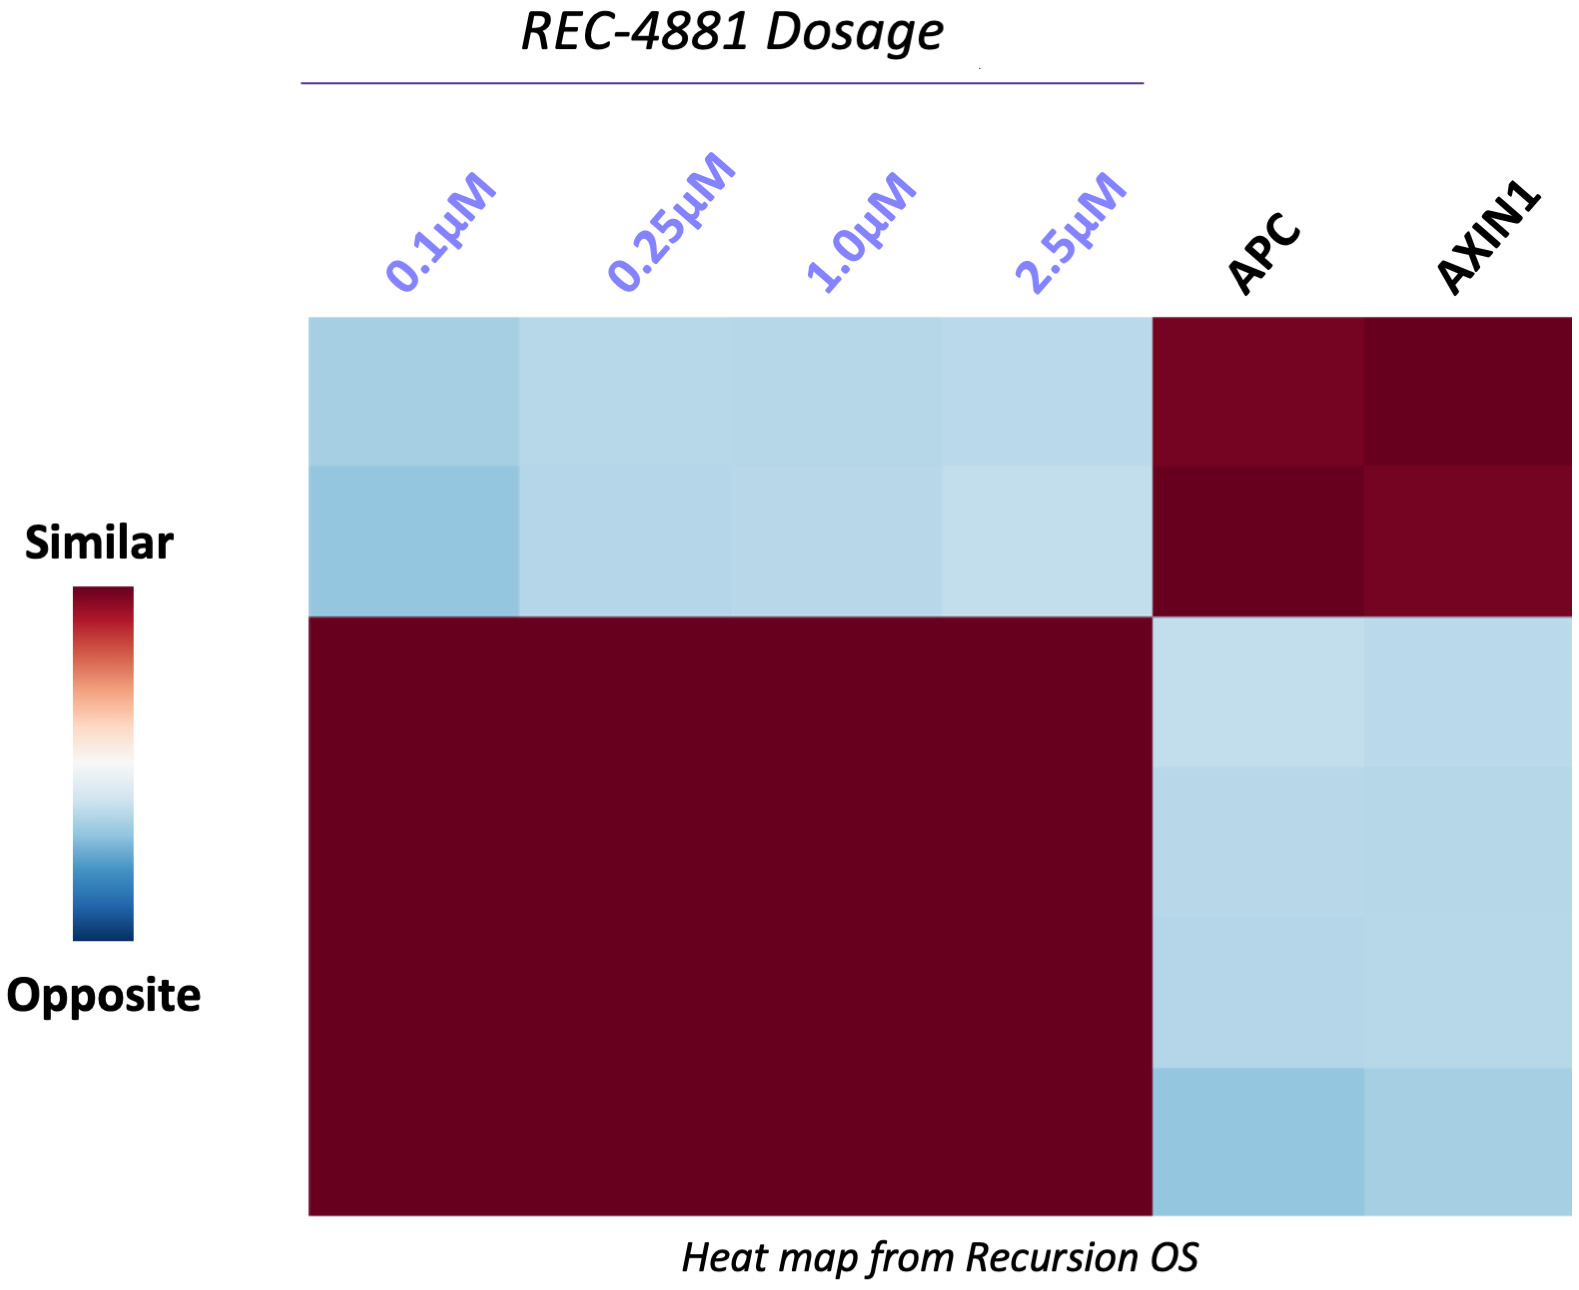

•Five phase 2 clinical-stage programs with multiple upcoming data readouts expected, including REC-994 in cerebral cavernous malformation (CCM) in Q3 2024, REC-2282 in neurofibromatosis type 2 (NF2) in Q4 2024, REC-4881 in familial adenomatous polyposis (FAP) in H1 2025, and REC-4881 in AXIN1 or APC mutant solid tumors in H1 2025